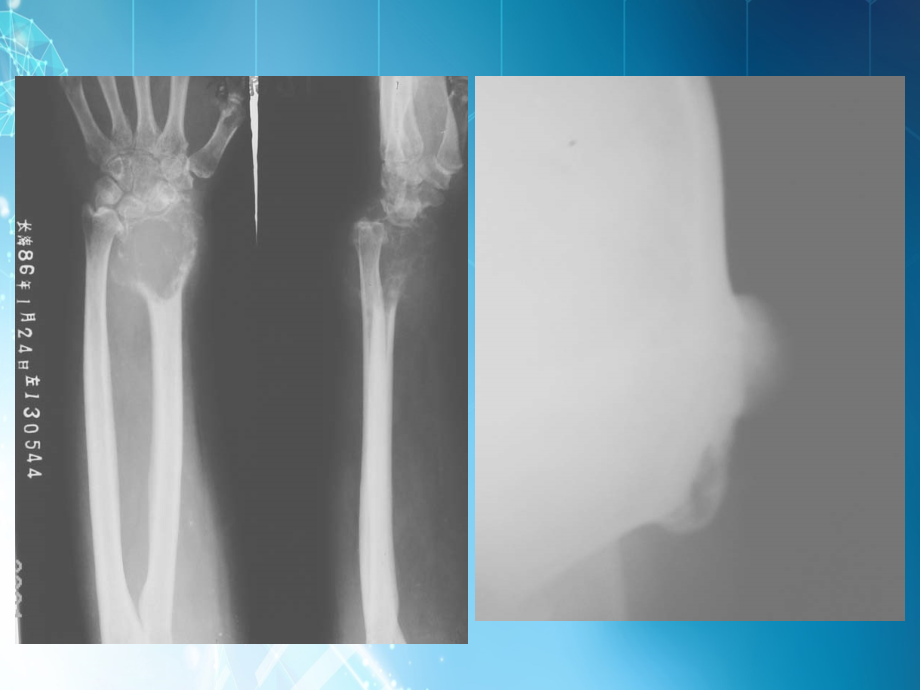

,第五节 骨 肿 瘤,骨 肿 瘤?,骨肿瘤是指在多种不同因素(内在、外在)的共同刺激下,导致骨组织本身或附属于骨的其它组织细胞,异常,的,新生,细胞群。,骨 肿 瘤,良性 过度 恶性,骨瘤 骨软骨瘤 巨细胞瘤 原发 转移,线检查的作用:,1、可显示肿瘤的部位、判断,良、恶性。,2、可区分是原发或转移。,3、确定治疗方案、估计预后。,病变部位,病灶数目,肿瘤边缘,骨质改变,有无骨膜,有无增生,软组织变化,临近骨情况,观察骨肿瘤时,一、良性骨肿瘤,(一)、,骨瘤,:,起自膜化骨。(颅骨、面骨),好发部位:颅骨及副鼻窦内。,线表现:,瘤体为密度均匀一致、轮廓光,滑的圆形或半圆形高密度影,基底,宽广,向外生长。,分单发及多发二种,单发多见,占90,好发1020岁的青少年,直至全身骨骺线融合后即停止生长。,(二)、骨软骨瘤,又称外生骨疣,骨质组成的基底和瘤体,软骨组织组成的盖帽,(,其生长有赖于此,),纤维组织形成的包膜,病 理,肿瘤的基底部可宽窄一与骨干相连,骨皮质由骨干延续至肿瘤远端,瘤体内的骨松质与骨髓腔相连。,、单发性骨软骨瘤,线表现:,部位:,好发于长骨干骺端,自骨端向骨干方向生长的骨性肿块,向外突起,肿瘤基底部可宽窄不一,顶部有不规则钙化。,有家族性、遗传性,可起自婴儿,成年后停止生长。,线表现:,、累及多骨,常左右对称。,、长骨干骺端增粗,变形,皮质变 薄,骨疣向旁突出,外形不一。,、多发性骨软骨瘤,(三)、巨细胞瘤,常见,,,好发于青壮年,因其具有复发、恶变和转移倾向,故将其分为良、恶性之间的一种特殊类型。,巨细胞瘤,线表现:,、好发于长骨骨端,表现为密度,减低的溶骨性改变,偏心性膨胀性生,长,也可呈多房性透光区,似“肥皂”,泡状,与正常骨分界清楚。,、骨皮质因肿瘤膨胀而变薄,无,骨膜增生反应。,、很少穿破皮质进入关节。,二、恶性骨肿瘤,X,线特点:,1、边缘模糊,界限不清,形状不规则。,2、骨组织不规则破坏,常侵犯骨皮质。,3、瘤骨:象牙质,棉絮状,光芒状。,4、骨膜反应。,5、软组织肿块。,6、可破坏邻近骨。,成骨肉瘤,多见于青少年,好发于长骨的干骺端,发展快,转移早,预后差,死亡率高。,病理:,1 肿瘤周围无包膜,2 浸润性生长,侵犯软组织,3 瘤组织主要是瘤性骨组织和,类骨组织。,根据瘤骨组织的多少可分为:,2,、,溶骨型成骨肉瘤,3,、,混合型成骨肉瘤,1、,硬化型成骨肉瘤,(成骨型),肿瘤常起自骨膜下及骨皮质,向各个方向发展,侵犯骨皮质和骨松质。,(一)、硬化型成骨肉瘤,、,骨膜反应,平行型,葱皮型,三角型,线 表 现:,瘤骨,成骨肉瘤的组织学特征,有三种形态:,1).,象牙质,:为致密硬化,边缘尚清的肿瘤中央部分;,2).,棉絮状瘤骨,:边缘不清,常有环状钙化存在;,3).,针状瘤骨,;密度明显增高,为瘤组织侵犯软组织。,、,骨质变化,、软组织变化,可见软组织肿胀及肿块,常边界不清,肿块内可见团块状瘤骨及放射状骨针。,(二)、溶骨型成骨肉瘤,肿瘤常起自骨松质,以溶骨性破坏为主。,线表现:,大片状溶骨性骨质破坏区,界限不清,有三角形骨膜反应,瘤骨少或无。,(三)、混合型成骨肉瘤,介入上述二者之间,,有不同程度的骨膜反,应及骨质改变。,三、转移性骨肿瘤,转移途径:,血行、淋巴路、直接蔓延等。,特点,:,、多发;,、红骨髓处;,、无骨膜反应;,、肘、膝以远转移少见;,、软组织肿块少。,(一)、溶骨型,多见,以破坏为主,。,多发、圆形破坏,边界不清,似虫蚀状,也可呈边界不清的大片状骨质破坏区,多引起病理性骨折。发生在脊柱的转移瘤应与结核鉴别。,线表现:,转移瘤,:,椎体压缩变形,椎弓根破坏明显,椎间隙保留,骨质无疏松。,结 核:,椎间隙变窄或消失,相临椎体破坏,变形。,脊柱转移瘤与结核鉴别点,(二)、,成骨型,较少见,多为生长较缓慢的肿瘤转,移而来,如前列腺、乳腺及膀胱癌等。,好发部位,:骨盆及腰椎。,线表现,:,骨内片状、团块状、边界模糊的致,密影,骨的正常结构消失,常无骨膜反,应,也不侵犯软组织。,良性肿瘤 恶性肿瘤,骨的形态 大致不变,可有局部 由于破坏,新骨形成及骨折,,扩张突出畸型 骨的形态常有改变,骨的结构 尚能保留,呈膨胀性 不规则骨质破坏和瘤骨,形成,改变较大,肿瘤的边缘 界限清楚 大多不清楚,骨膜增殖 无 明显,呈放射或三角形骨膜,肿瘤附近骨 不受侵犯,可有 常受侵犯,可有骨质破坏,压迫性改变,附近软组织 不受侵犯 常被波及,广泛侵入,周围软组织中,生长速度 缓慢 迅速,病理骨折 少见 多见,转 移 无 常有转移,一,、,良恶性肿瘤的鉴别,1)、,颅缝分离,;,儿童为冠状缝和失状,缝,成人为人字缝。,2)、,脑回压迹,增多、加深;,3)、,颅板变薄,;,长期增高,可使颅骨,吸收,密度减低。,4)、,碟鞍改变,。,鞍背、后床突破坏,,骨质疏松,蝶鞍扩大,变形。,二、颅内压增高的线表现,